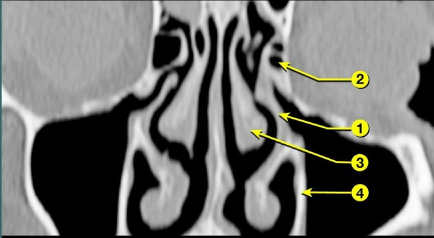

The structure marked as 1 is the _____ which is removed in infundibulotomy(FESS).